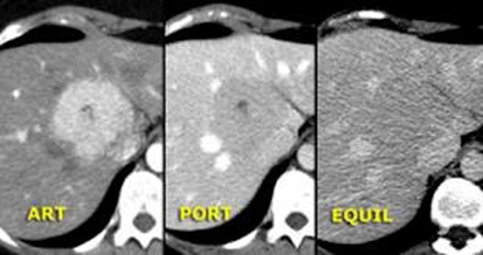

• NET-in qaraciyər metastazlarının xarakterik xüsusiyyəti hipervaskulyar olmasıdır ki, bu da Doppler müayinəsində intensiv axın şəklində, kontrastlı müayinələrdə isə arterial fazada kontrastlaşma və venoz fazada yuyulma əlaməti ilə təyin edilir.

Diaqnostik əlamətləri:

• Kütlə effekti və ya endokrin əlamətlər

• 5-hidroksiindol turşusu və ya hormonların artması

• Hipervaskulyar törəmələr